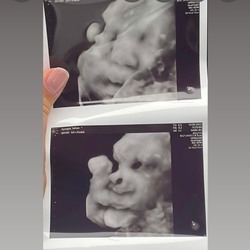

Ik ben net terug van de echo en mijn baby ligt er ook zo bij. De verloskundige heeft er alleen niets over gezegd, gewoon "oh ze ligt met haar gezichtje in de placenta" en de placenta ligt aan de voorkant. Dus nog niet echt reden tot paniek hoop ik! 😅